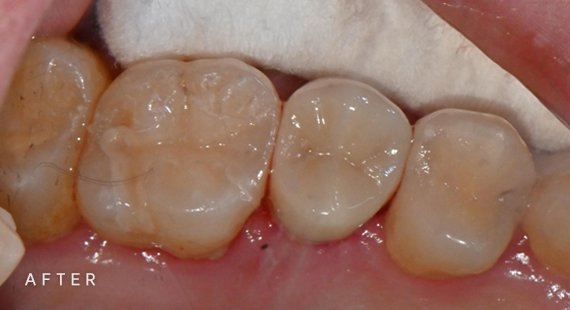

충치치료